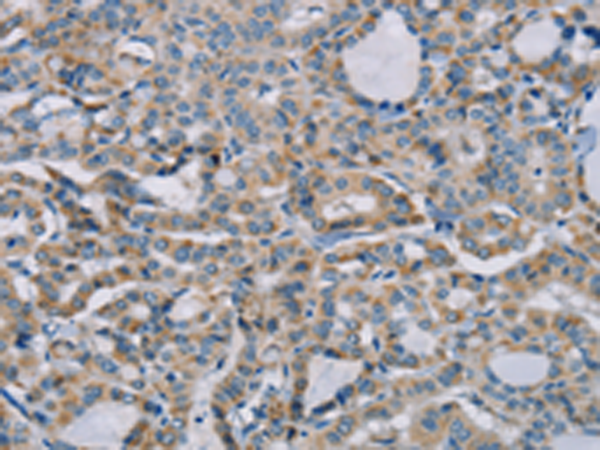

分类: 科研抗体货号: P08558别名: CI-13kA; CI13KDA; CI-13kD-A应用: IHC反应种属: Human, Mouse, Rat